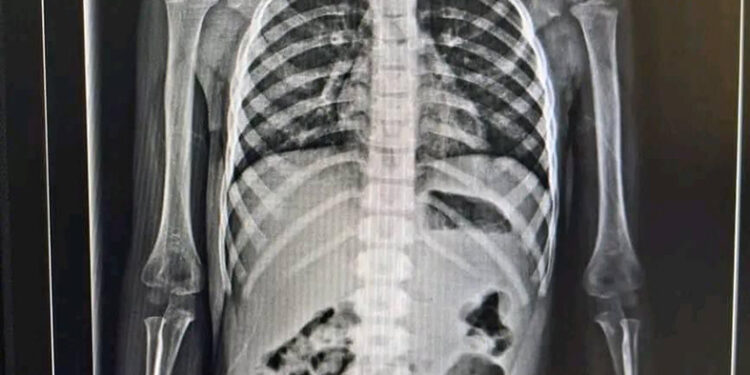

Una niña de nombre Yaritza “N”, originaria de Ocosingo, accidentalmente se tragó una figura de metal y de acuerdo a los resultados médicos, su vida está en riesgo, y que es difícil retirar el objeto.

Fue traída de emergencia al hospital de San Cristóbal, sin embargo, no pudieron hacer nada ya que la figura no se puede sacar por la vía de la boca.